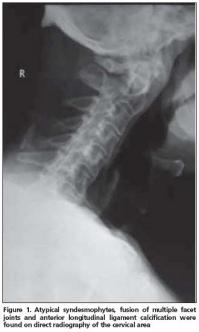

Anterior longitudinal ligament calcification, fusion of multiple facet joints and atypical syndesmophytes were found on cervical spine X-rays (Figure 1) and coarse, asymmetrical syndesmophytes were seen on thoracic (Figure 2) and lumbar spine (Figure 3) X-rays. No abnormalities suggesting PsA or gout were seen on hand and foot radiographs. The magnetic resonance imaging (MRI) of the sacroiliac joint and computerized tomography (CT) of atlanto-axial joint were normal.

Another striking radiologic finding in our patient was that cervical spine involvement was on the foreground. Queiro et al. reported the cervical spine involvement in HLA-B27- negative PsSpA patients to be 51%[13]. Cervical spine involvement in PsA is known to be seen more commonly in patients presenting with psoriatic lesions on hairy skin[12]. The majority of skin lesions were localized on the hairy skin in our patient. Radiographic abnormalities are not sufficiently sensitive and specific for the diagnosis of gout. Only 45% of patients with gout manifest radiographic bone changes, and then only six to eight years after the initial attack. The radiographic hallmarks of gout are normal mineralization, joint space preservation, sharply marginated erosions with sclerotic borders, overhanging edges, and asymmetric polyarticular distribution[14]. Radiologic evaluation of our patient did not reveal any of these images.